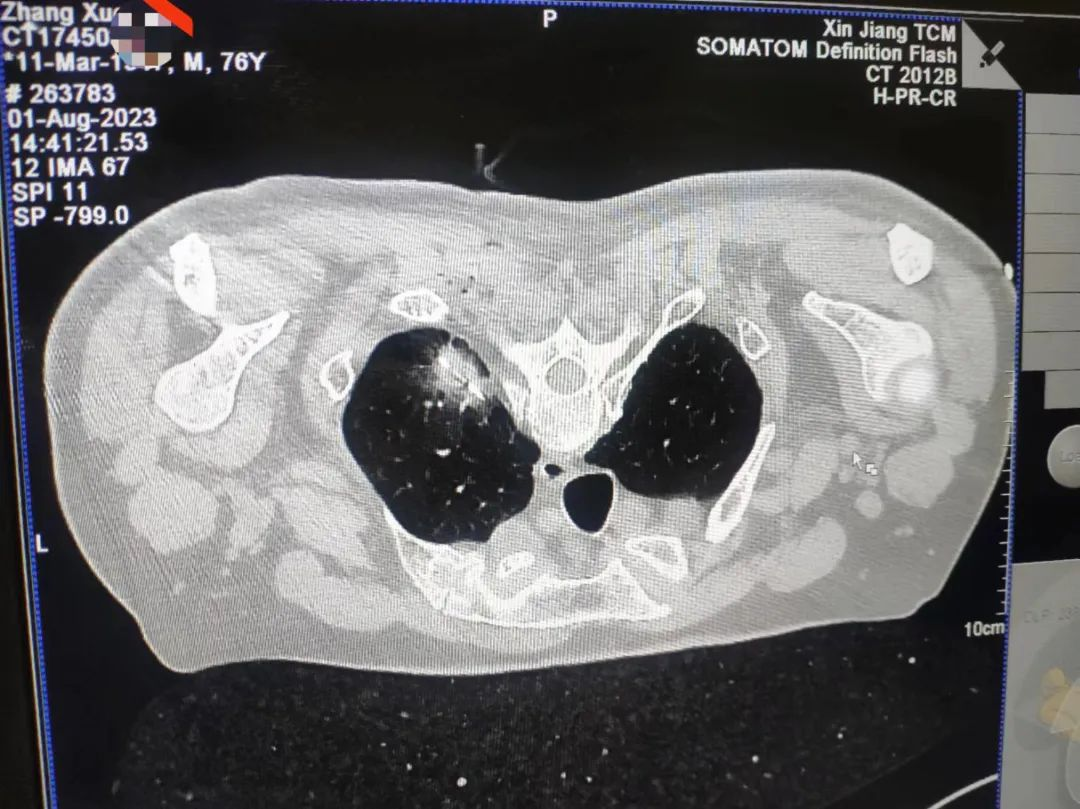

丁先生今年76岁,12年前曾经因结肠癌实施了手术,最近因身体疲劳来医院检查,发现左肺上叶2*2㎝不规则结节,呼吸一科为丁先生做了经皮肺结节活检术,术后病理诊断肺腺癌,考虑到既往患者有结肠癌手术史及慢阻肺病史,医生与丁先生及家人充分沟通后,决定行经皮穿刺肺部肿瘤微波消融术,术后患者未出现气胸及胸腔出血等并发症。

术后一个月,丁先生再次来我院复查:可见患者消融区域呈现空洞液化坏死,患者无不适主诉,根据微波消融相关指南共识及文献报道,该患者疗效满意,期待该患者下次复查结果。